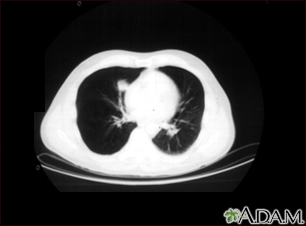

Lung nodule, right lower lung - CT scan